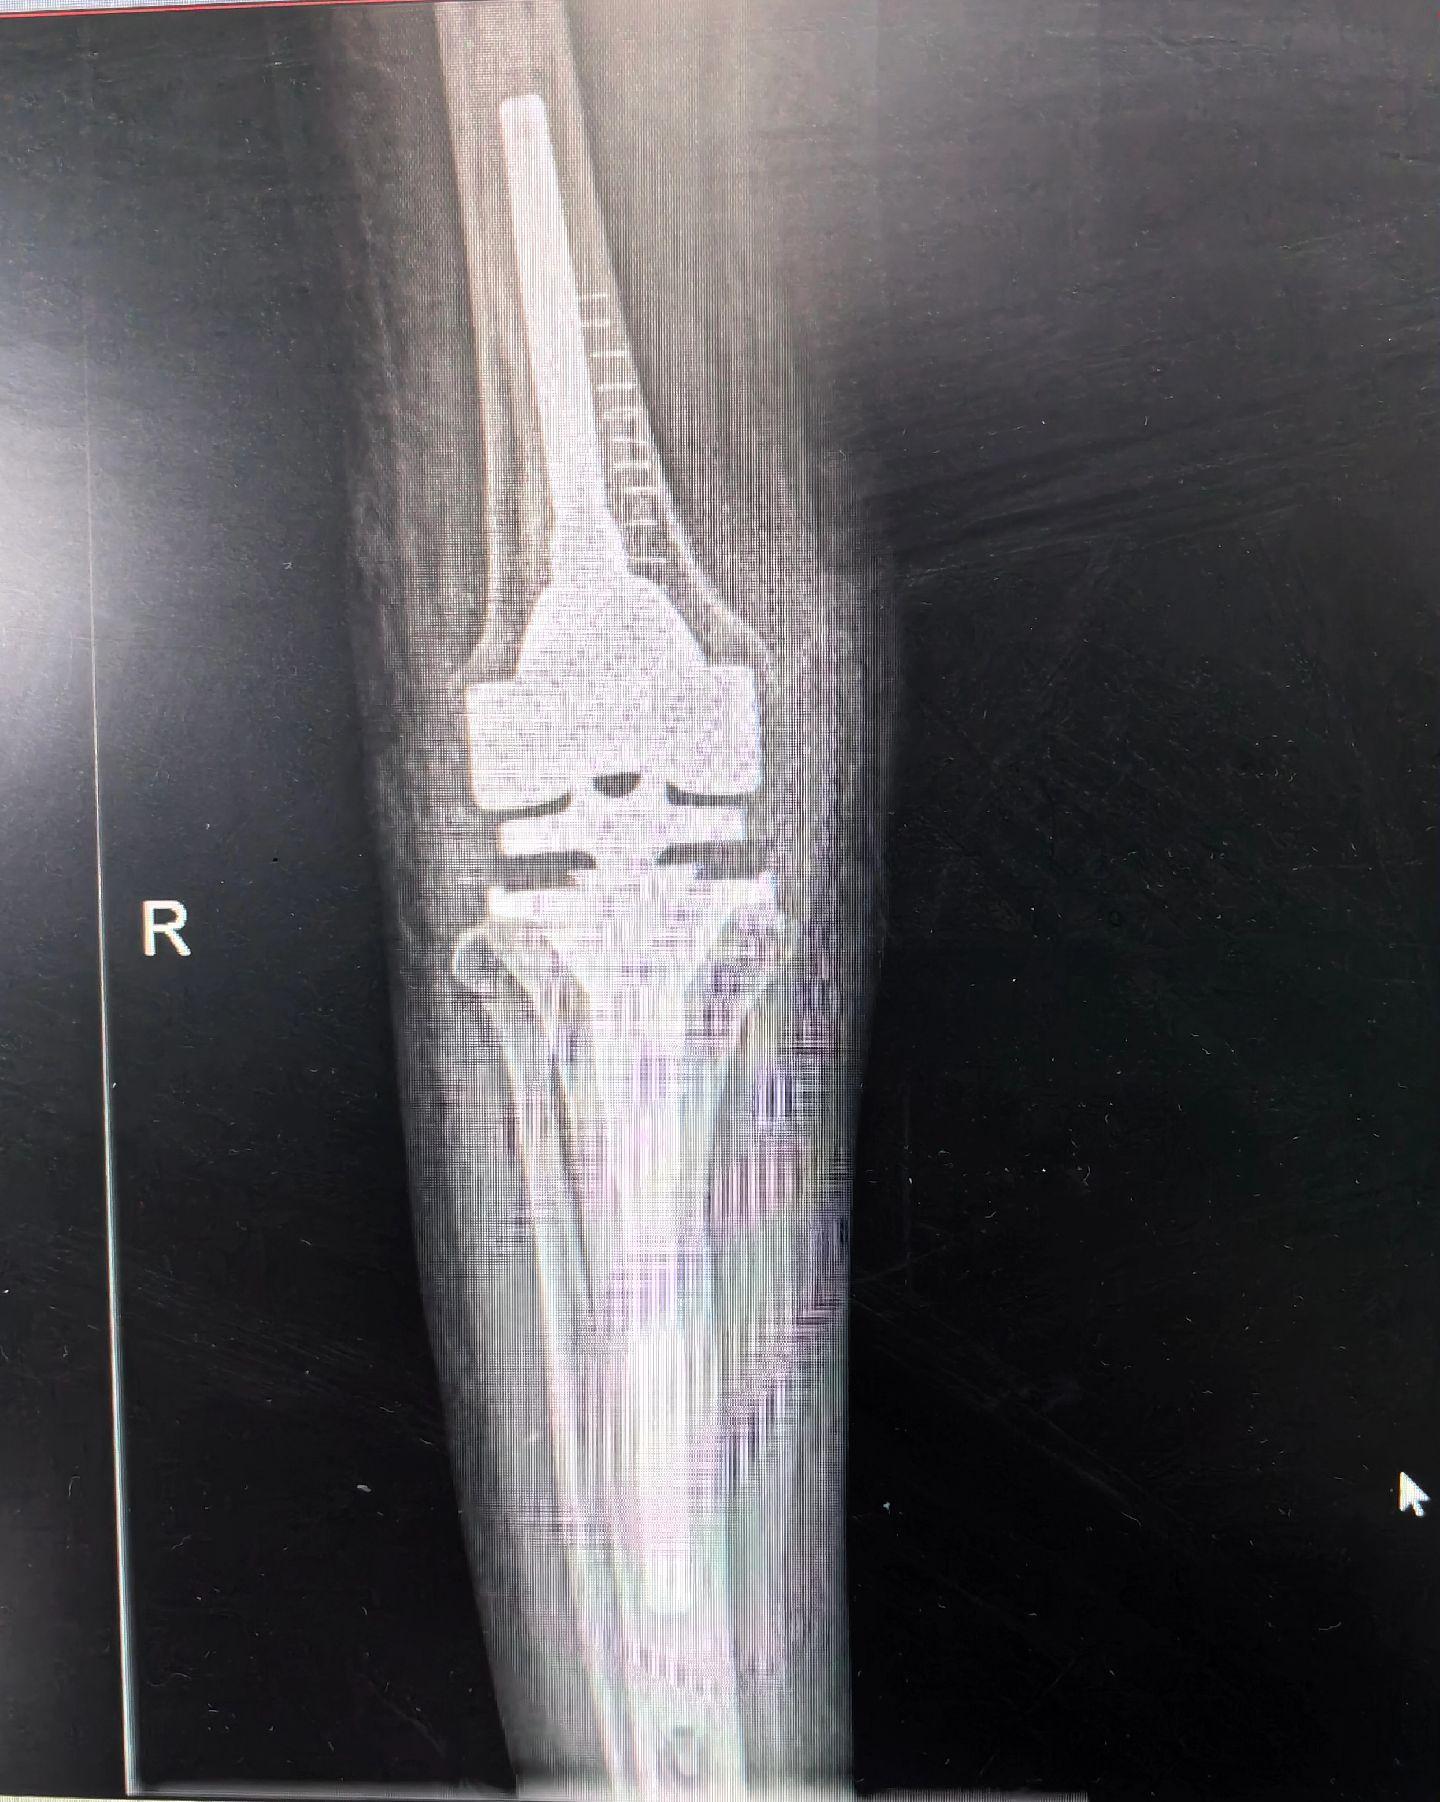

膝关节翻修。PJI,二期翻修。关节置换,谨防感染。